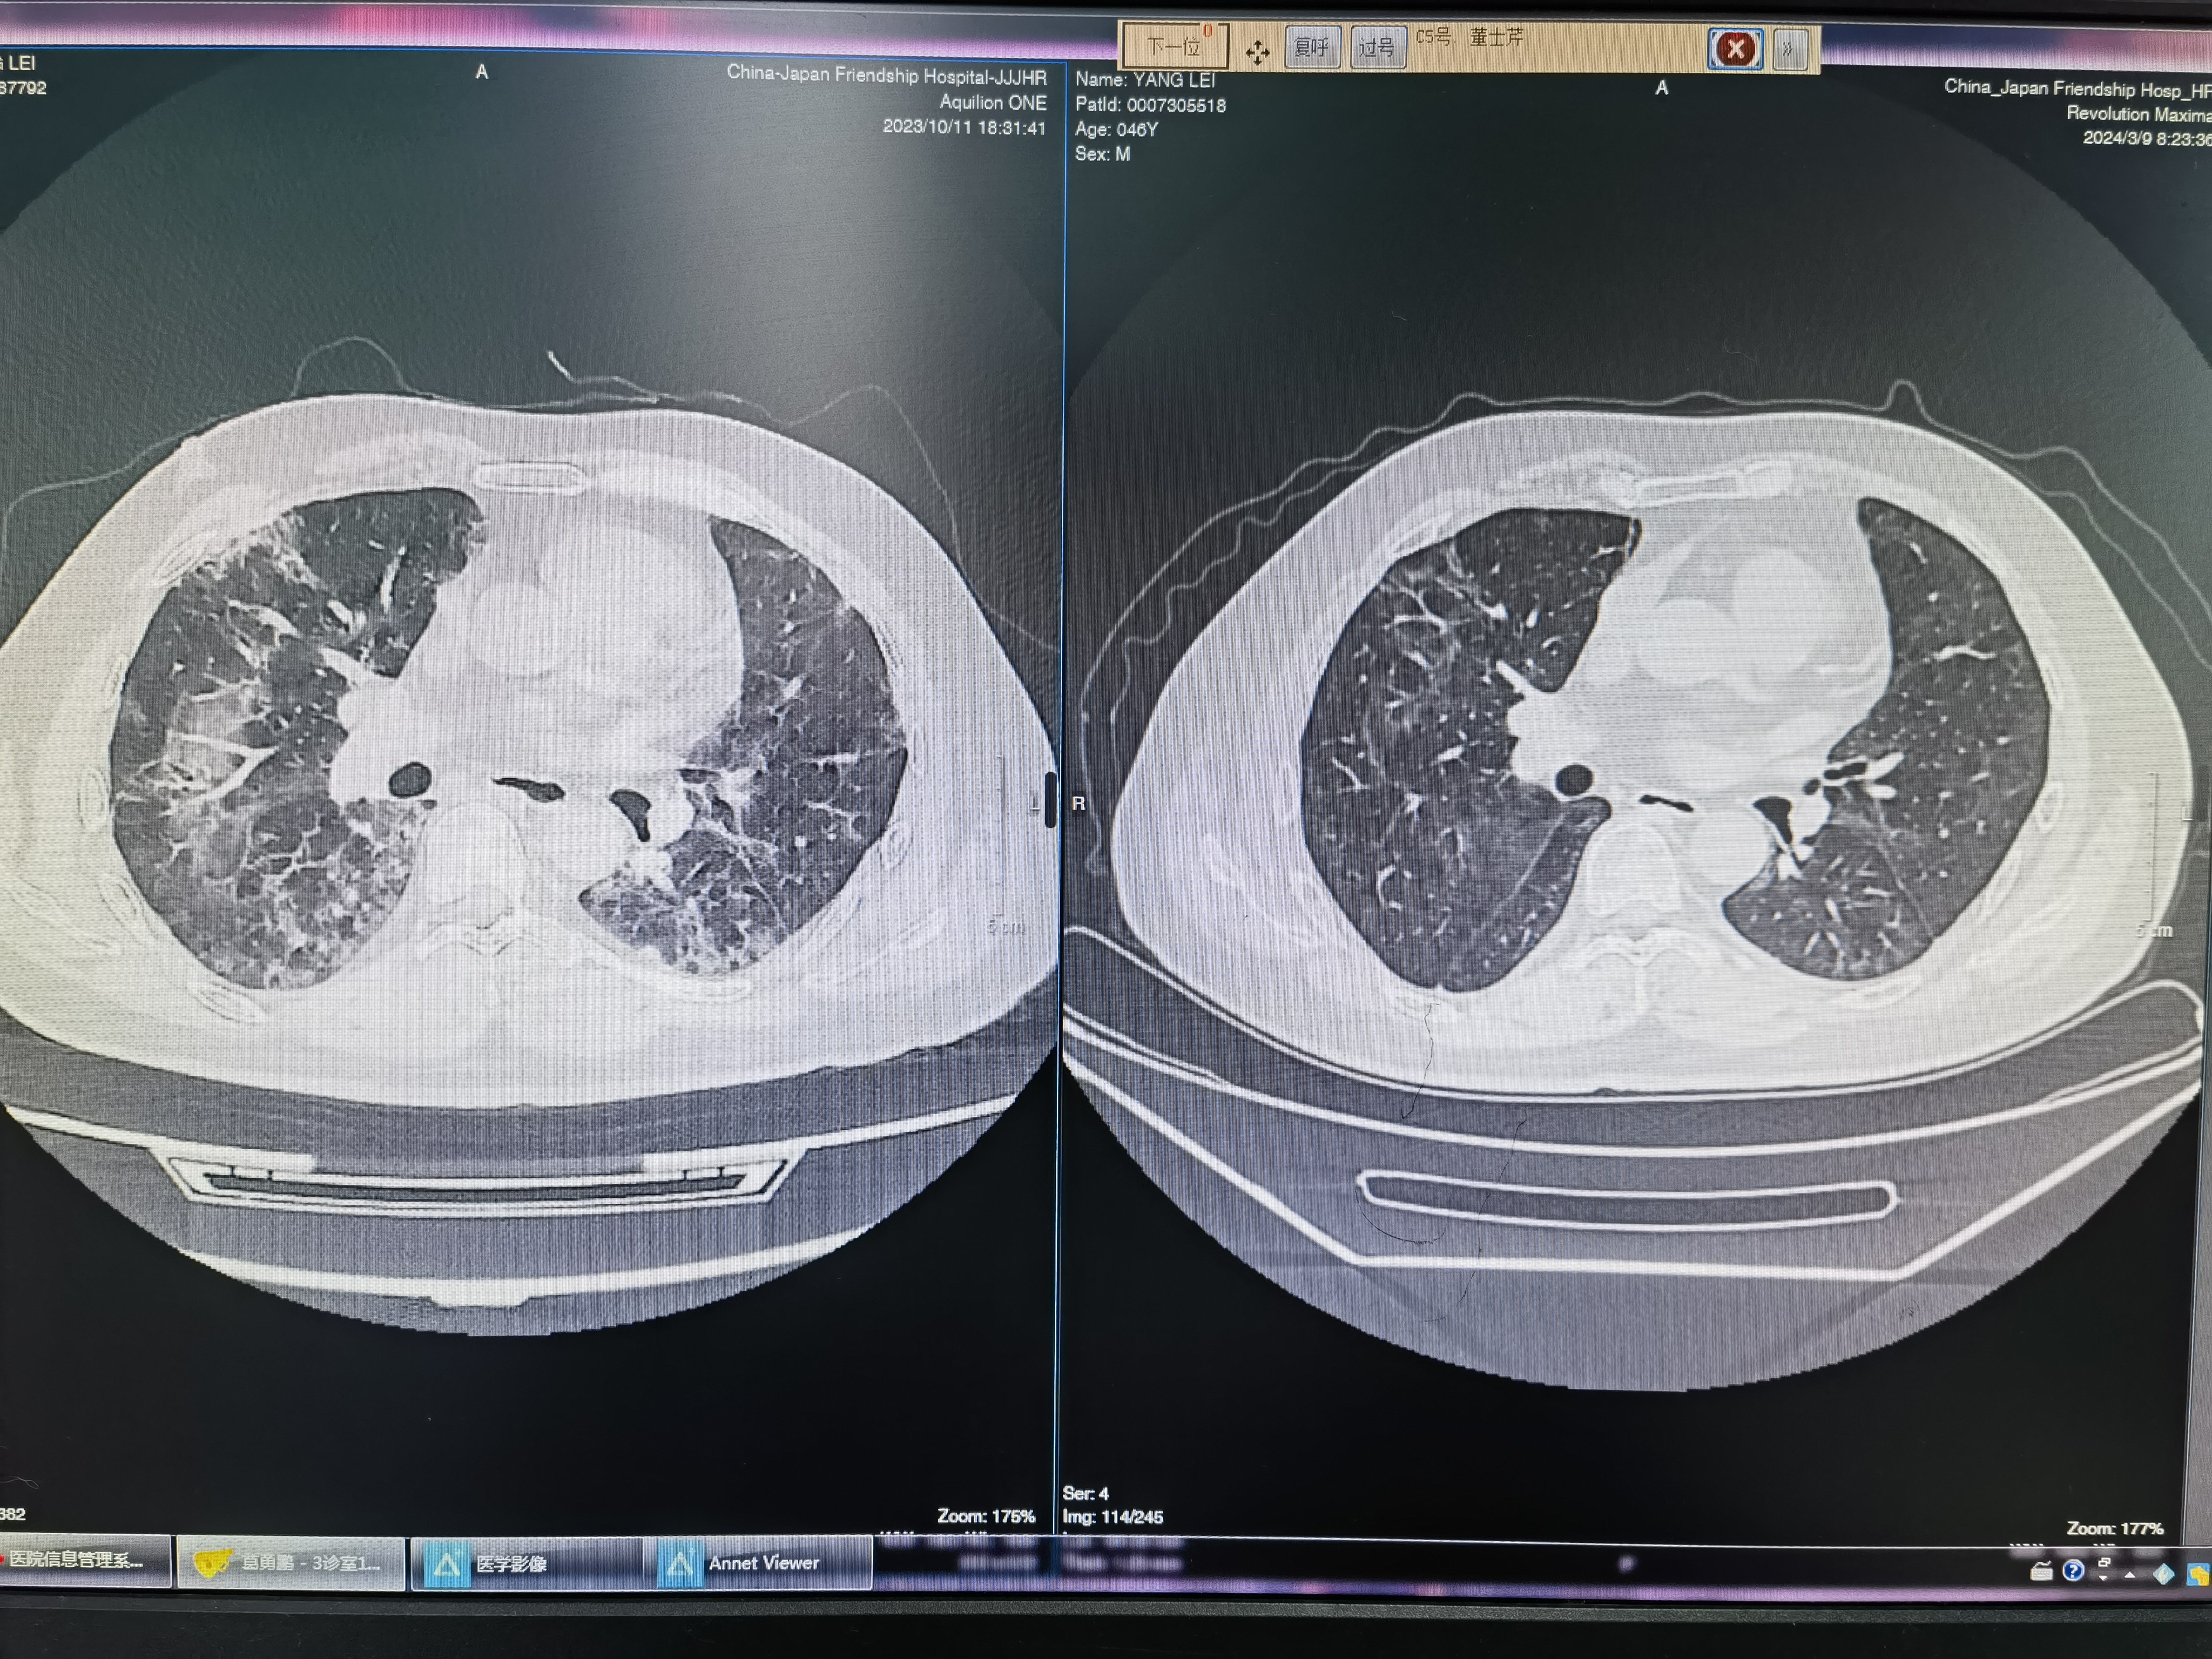

難治性抗合成酶綜合征

中年男性,有技工手,肌酶升高,呼吸困難,CT提示肺間質(zhì)病變,與院外先后經(jīng)過環(huán)磷酰胺,他克莫司、環(huán)孢素等治療1年余,病情時(shí)有復(fù)發(fā),呼吸困難逐漸加重,CT提示病變?cè)龆?。入院后充分評(píng)估病情,根據(jù)患者自身病情特點(diǎn),給予激素聯(lián)合JAK抑制劑后,病情很快好轉(zhuǎn)。最近的感悟:每個(gè)抗合成酶患者都要遵循個(gè)體化的原則,找到合適的治療方案,病情改善快,減輕患者痛苦,并且能夠大大降低治療費(fèi)用。